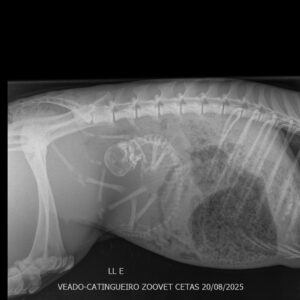

O cervo chegou muito debilitado e foi atendido com urgência, sendo realizado todos os procedimentos necessários para estabilizar o quadro de saúde.

Ao realizar um ultrassom, a equipe do médico veterinário Rômulo de Castro descobriu que a fêmea de veado estava prenha.

Mãe e filhote ficaram em observação na clínica Zoovet.